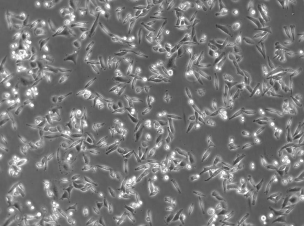

| 细胞形态 | 上皮细胞样 |

| 生长特性 | 贴壁生长 |